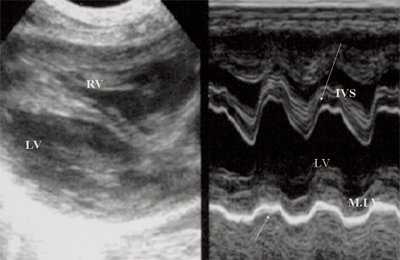

Рис. 1. Систолическая перегрузка правого желудочка. Поперечное сечение желудочков сердца при стенозе легочной артерии. Градиент давления правый желудочек - легочная артерия равен 200 мм рт.ст. Выраженная гипертрофия межжелудочковой перегородки и миокарда передней стенки правого желудочка.

Характерными особенностями выраженной объемной перегрузки правого желудочка являются дилатация желудочка, при которой толщина миокарда не превышает верхней границы нормы, увеличение правого предсердия, парадоксальный характер движения межжелудочковой перегородки и увеличение амплитуды движения трикуспидального клапана (рис. 2, 3).

Рис. 2. Длинная ось сердца. Объемная перегрузка правого желудочка при дефекте межпредсердной перегородки. Объем сброса крови превышает 200% МОС. Отмечается выраженная дилатация правого желудочка.

Рис. 3. Объемная перегрузка правого желудочка при дефекте межпредсердной перегородки. В- и М-сканирование. Стрелкой показан парадоксальный характер движения межжелудочковой перегородки.

Для левого желудочка признаком объемной перегрузки являются увеличение полости левого предсердия и желудочка, а также экскурсии межжелудочковой перегородки и миокарда задней стенки левого желудочка (рис. 4).

Рис. 4. Объемная перегрузка левых отделов сердца. В- и М-сканирование. Отмечается усиление экскурсии межжелудочковой перегородки и миокарда задней стенки левого желудочка.

IVS - межжелудочковая перегородка, MLV - миокард левого желудочка, LV и RV - левый и правый желудочек.